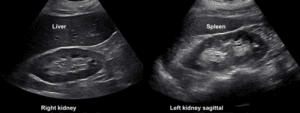

Venous excess Doppler ultrasound (VExUS) grading system

The VExUS grading system is calculated following the steps of the original paper. First the IVC is measured and, if bigger than 20 mm, the portal, hepatic and intrarenal veins are scanned. Doppler interrogation of these vessels yields a specific pattern corresponding to a level of venous congestion: normal, mild, or severe. According to the results, the VExUS score is obtained as follows: VEXUS 0: IVC < 20mm; VEXUS 1: IVC ≥ 20mm with normal patterns or mild abnormalities; VEXUS 2: IVC ≥ 20mm with severe abnormality in at least one pattern and VEXUS 3: IVC ≥ 20mm and severe abnormalities in multiple patterns.

Considering the technical difficulties in achieving the best ultrasound images for this protocol, the authors allow the use of the best window and view consider by the operator.